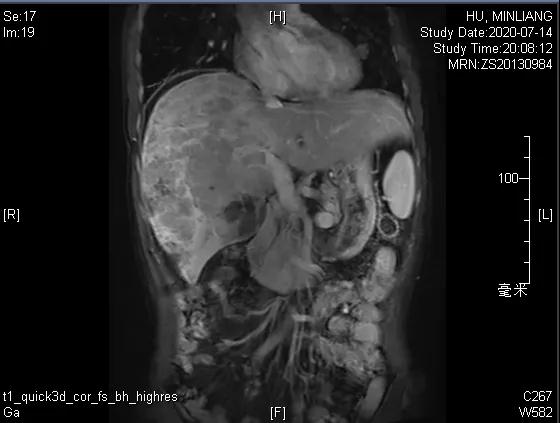

肝脏弹性超声:12kPa。腹部MRI平扫+增强:肝巨块结节性HCC(最大径18.4cm)伴肝内多发转移(最大径3.5cm),肝右静脉广泛癌栓形成;肝硬化伴门脉高压、脾大、少量腹水;肝囊肿;双肺多发转移。胸部CT平扫:两肺多发转移,两肺气肿伴肺大泡,两肺散在慢性炎症,右侧少量胸水。

Δ肝脏MRI,最大肿瘤18.4cm